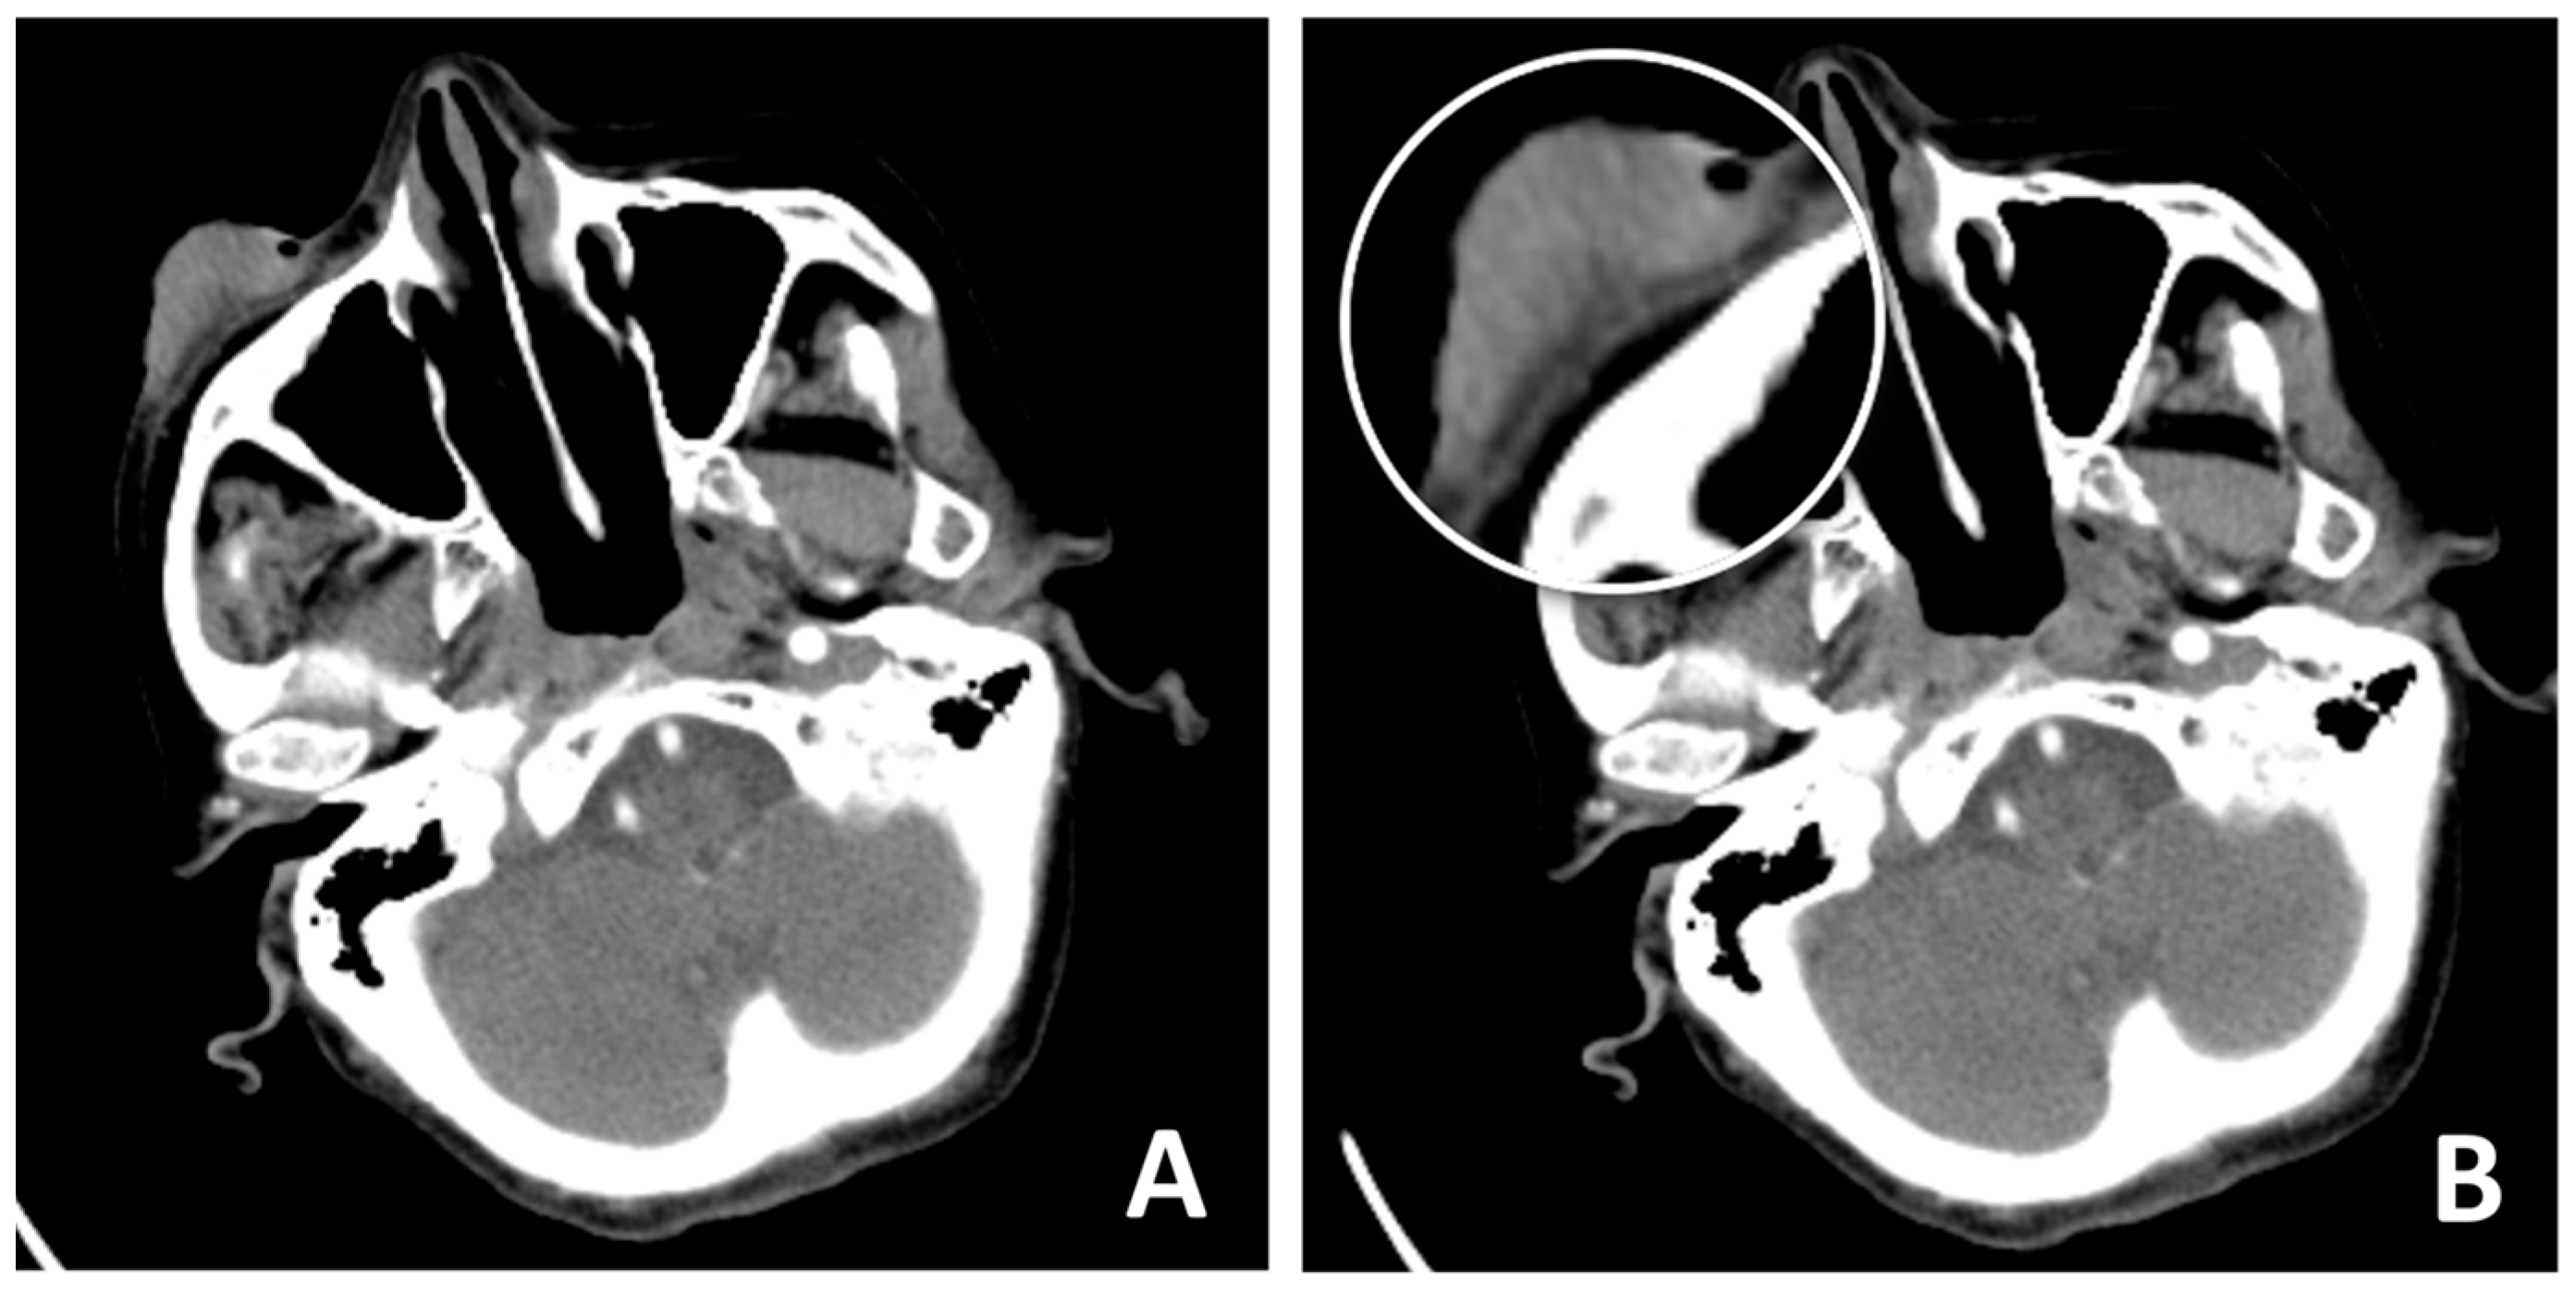

2. Case Presentation